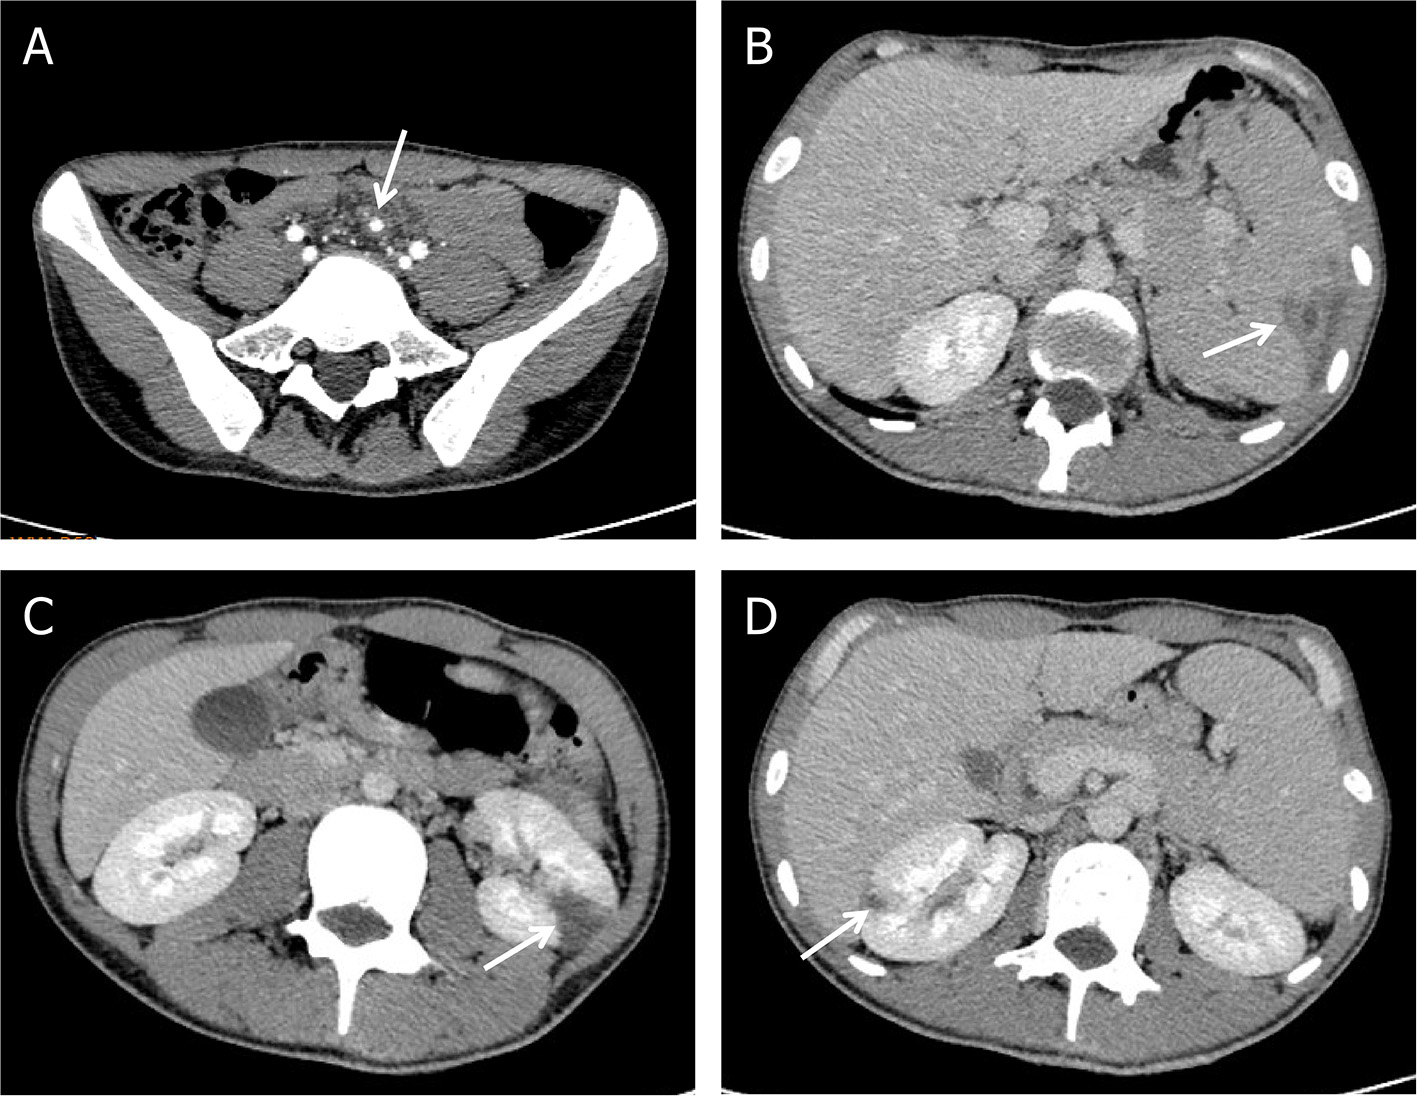

While during the therapy, he developed progressively worsening abdominal pain with left upper quadrant tenderness to palpation. Contrast-enhanced abdomen CT demonstrated mesenteric arterial branch aneurysms and splenic and renal infarcts (Figure 3).

Figure 3

Complications of Abiotrophia defectiva infective endocarditis. (A) Mesenteric arterial branch aneurysms in abdomen CT. (B) Splenic infarction in abdomen CT. (C,D) Multiple renal infarction in abdomen CT.